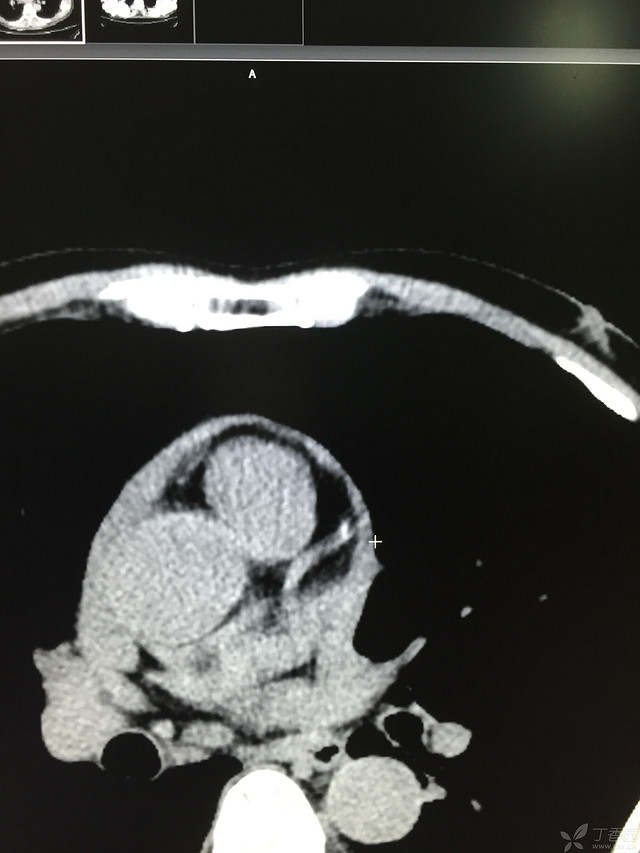

胸痛三天,加重三小时(CT是心包高密度影是什么)

患者性别:男

患者年龄:64岁

简要病史:三天前休息时突发胸前区疼痛伴大汗,到当地医院输液治疗后缓解,3小时前情绪激动后再次出现胸痛伴大汗,胸部压迫感,持续不缓解入院,到当地医院测血压180/?mmHg泵入硝酸甘油转入我院。

体格检查:血压94/72mmHg(右侧)96/74mmHg(左侧),心率78此/分,其他未见阳性体征